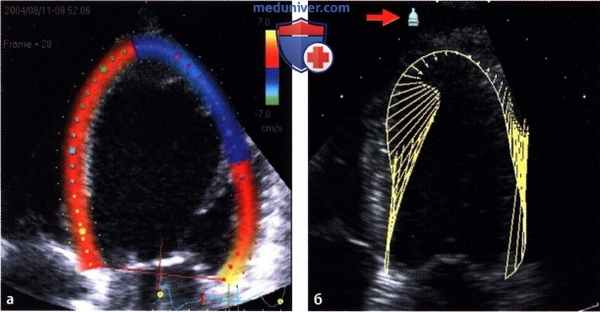

Режим отслеживания пятна (SpeckleTracking). В текстуре миокарда автоматически распознаются характерные паттерны (например, светлые точки изображения) и отслеживаются от кадра к кадру.

Их пространственное смещение соответствует движению миокарда. Так как частота кадров известна, можно рассчитать и скорость движения.

Если одновременно отслеживать много разных паттернов, можно соответственно рассчитать деформацию и скорость деформации.

Возможности изображения двумерной информации о движении:

а - На картинке слева в цветовой кодировке отображается скорость. Направление изучаемого компонента движения можно выбрать в меню (здесь: продольный).

б - В качестве альтернативы движение можно представить в виде векторных стрелок. Сама стрелка указывает направление движения, а ее длина отражает скорость смещения.

Для получения кривых и в этом случае необходимо задать направление исследования, перемещая символ датчика (стрелка).

4. Изображение многомерного движения. Возможность многомерного анализа движения и деформации порождает новую проблему: как это изобразить. Поскольку при помощи цветовой кодировки можно изобразить только один параметр - в данном случае движение в одном определенном направлении, то пользователь должен выбрать интересующее его направление движения.

В современных программах цветокодированное изображение, как правило, ограничивается представлением продольной или трансмуральной функции. Другие производители полностью отказываются от цветовой кодировки и представляют движение (эндокарда) в виде векторных стрелок (режим изображения векторов скорости, «Vector Velocity Imaging»). В таком случае для отображения определенного компонента движения в виде кривых пользователь может произвольно задать точку отсчета.